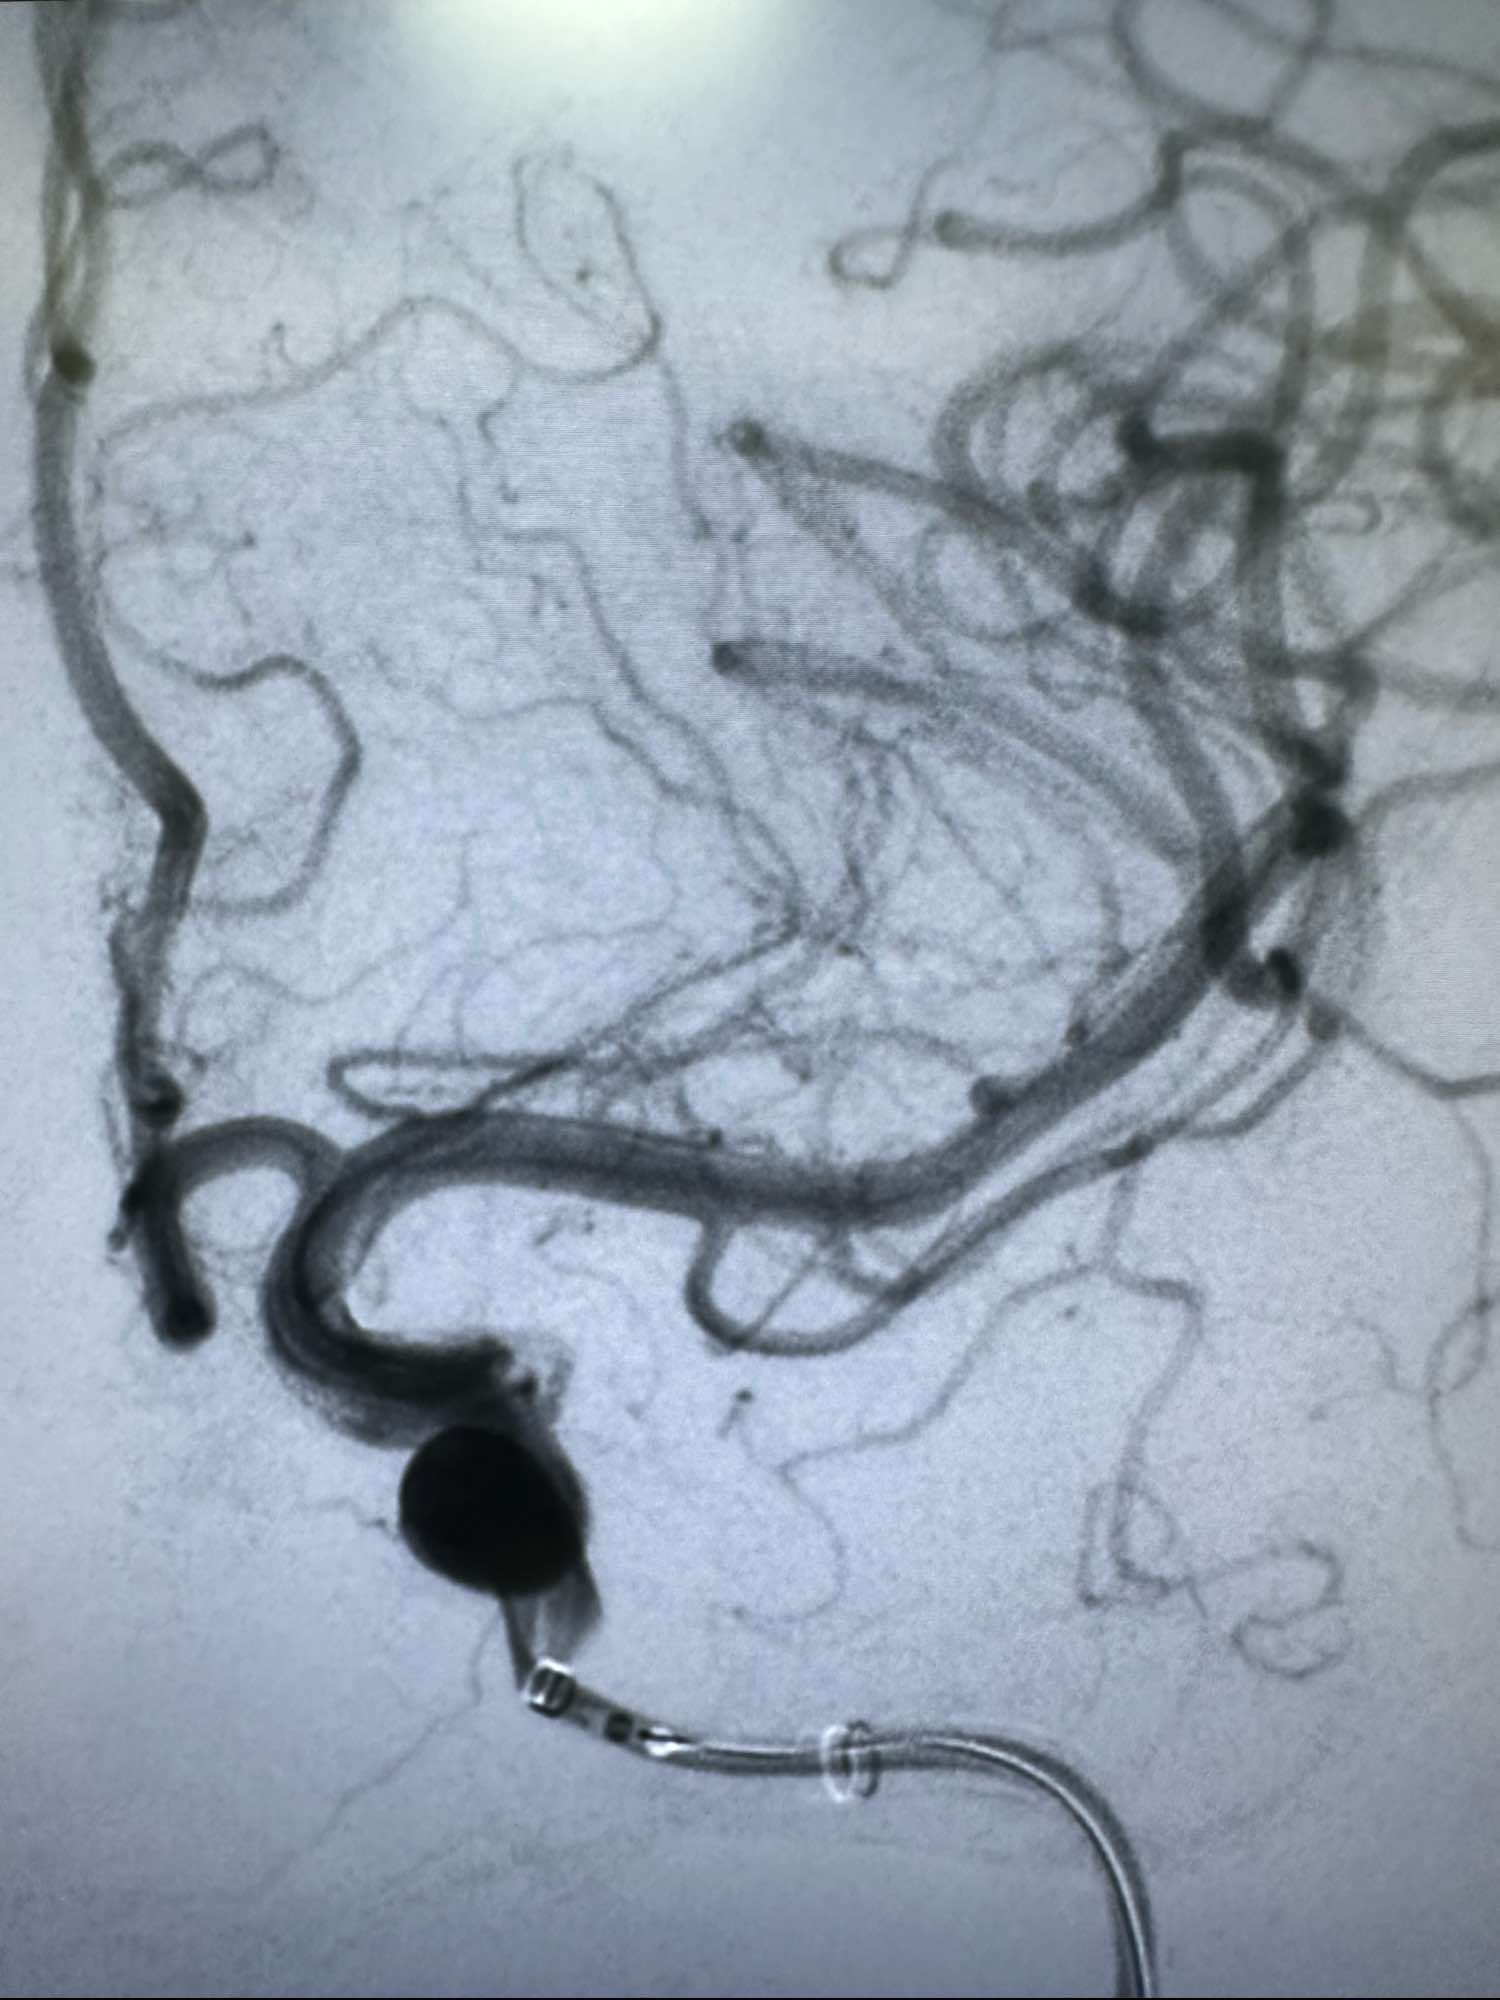

左侧颈内动脉造影正位